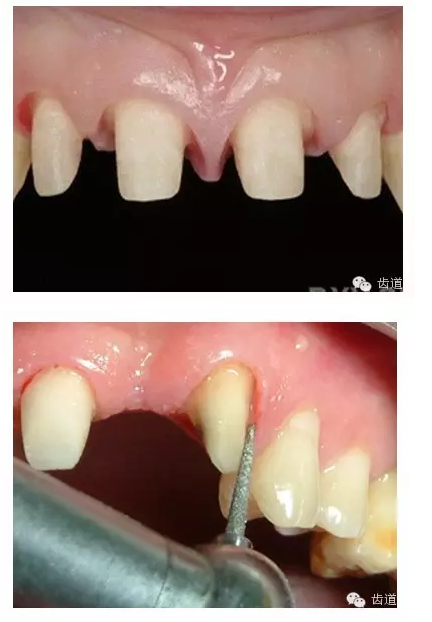

牙體預備的基礎(chǔ)知識大全

l保護牙體組織

l邊緣的適合性

l保護牙周組織